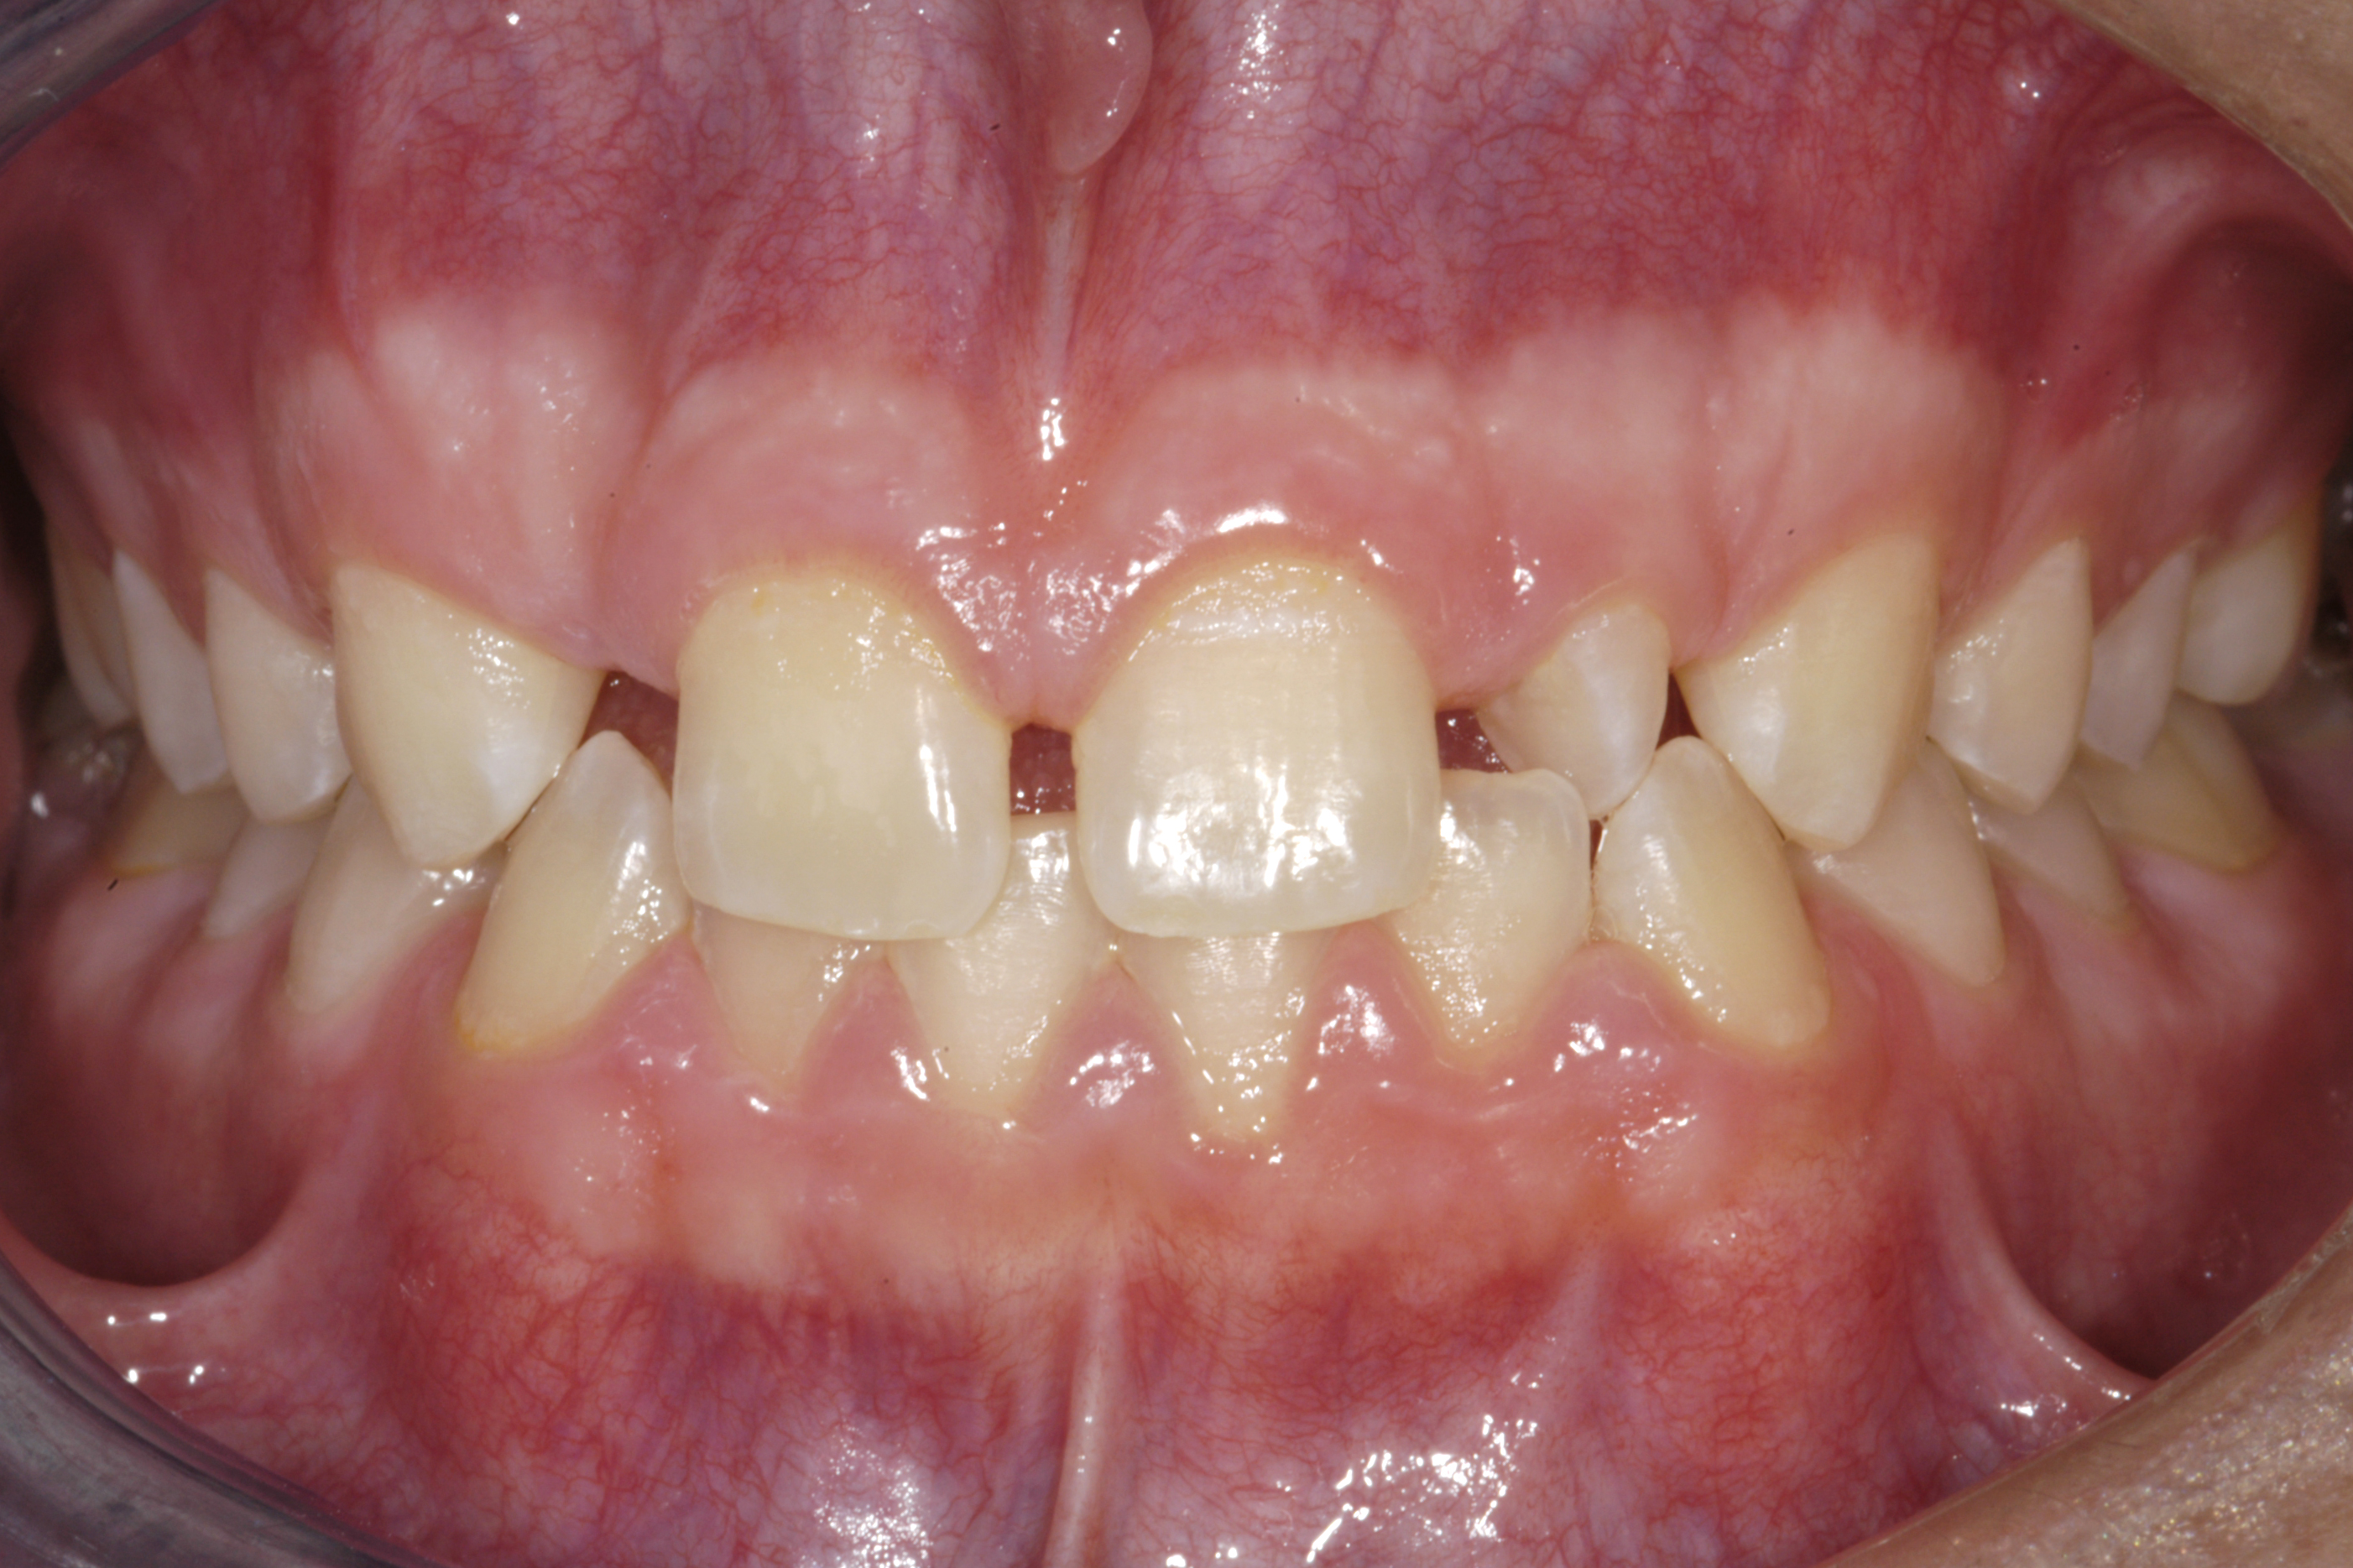

(12.) 15-year-old girl after orthodontic therapy idealized maxillary lateral incisor spaces.

Figure 12

(13.) Deficient ridges in the areas of the missing lateral incisors.

Figure 13

(14.) Occlusal view. Some form of augmentation would be needed if implants were being considered.

Figure 14

Some patients do not want an implant due to the need for surgical intervention, and others may not have enough space for implant placement. A 15-year-old patient presented to the office after completion of orthodontic treatment to idealize the spacing of her teeth and improve her occlusal relationship (Figure 12 through Figure 14). Because both of her maxillary lateral incisors were missing, the patient was wearing a retainer with lateral incisor pontics. She had a busy school schedule, but expressed her desire for a fixed restorative option. All of her options were discussed, and the patient was informed that if she wanted an implant, she would have to wait for at least 3 to 4 years for completion of growth. The patient was not sure if or when she wanted to have an implant placed in the future, especially considering her busy schedule and desire to attend college after high school. Considering her age and the need to be conservative, a single-wing zirconia Maryland Bridge was chosen as the ideal prosthetic replacement option. Because bonding a non-etchable and smooth surface such as zirconia requires chemical adhesion, it was decided to use a modified technique to make the bridge more retentive. One of the ways to improve adhesion of a zirconia bridge is to use an etchable feldspathic ceramic layer on the internal surface of the zirconia retainer.56-58 Unfortunately, it can be difficult to determine the thickness of the ceramic and ensure accurate seating of the restoration.